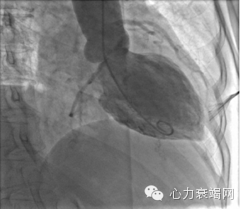

#2.入院后患者行冠状动脉造影,影像学显示轻度冠状动脉远端病灶;行左侧脑室RAO视图,示收缩期心室功能异常

心导管检查显示左心室造影收缩时,中室与顶端收缩膨胀。